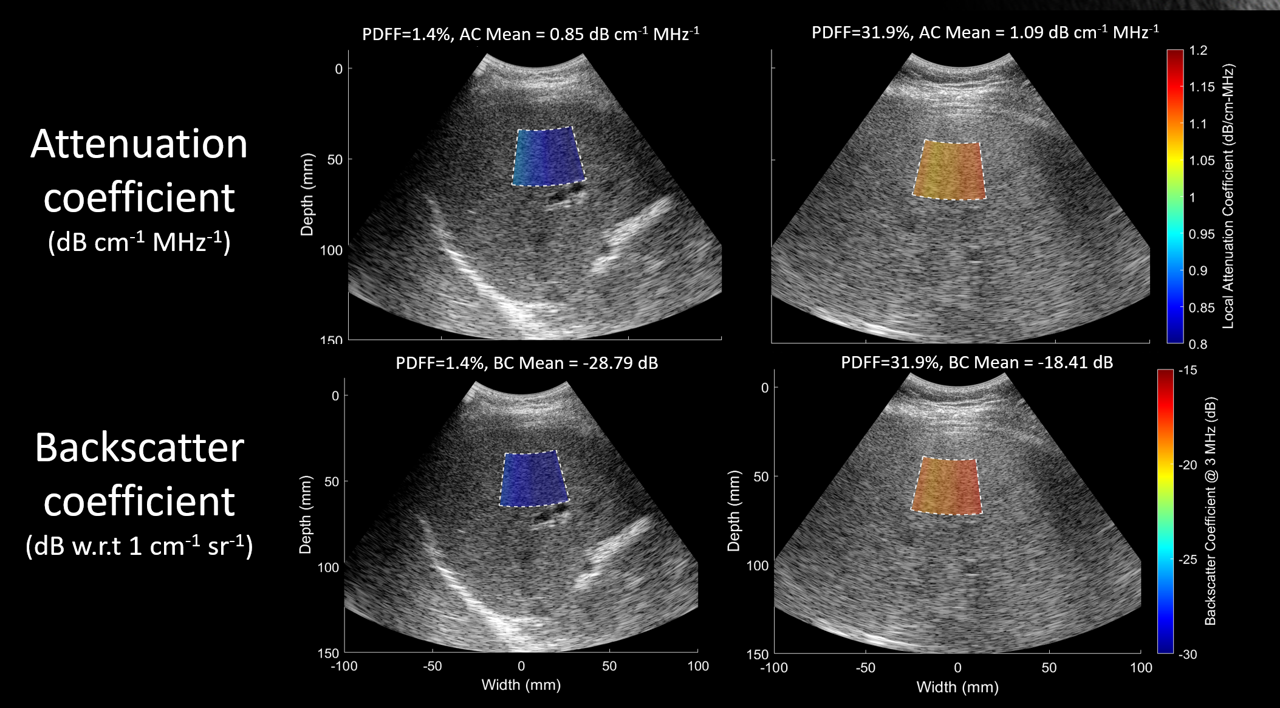

Ultrasound plays an important role in the evaluation of diffuse liver disease, like the deposit of fat in hepatocytes (steatosis) or the deposition of fibrous tissue (fibrosis). As these problems become more common due to the increasing prevalence of overweight and obesity, reliance on ultrasound for patient management become more important due to its widespread availability. However, conventional B-mode imaging is highly operator and observer dependent and is not sensitive to initial stages of the disease. Working with Dr. Scott Reeder (UW-Madison) and Dr. Claude Sirlin (University of California, San Diego), we are exploring the value of quantitative ultrasound and shear wave elastography to provide biomarkers of liver steatosis and fibrosis in patients undergoing bariatric surgery. In collaboration with Dr. Diego Hernando (UW-Madison) we are investigating sources of variability in QUS applied to the pediatric liver. In parallel, as part of our contribution to the Quantitative Imaging Biomarkers Alliance, we are helping develop standardized guides for implementing these techniques in clinical practice, in order to ensure their successful translation.

Fetzer DT, Rosado-Mendez IM, Wang M, Robbin ML, Ozturk A, Wear KA, Ormachea J, Stiles TA, Fowlkes JB, Hall TJ, Samir AE. Pulse-echo quantitative US biomarkers for liver steatosis: toward technical standardization. Radiology. 2022 Nov;305(2):265-76.